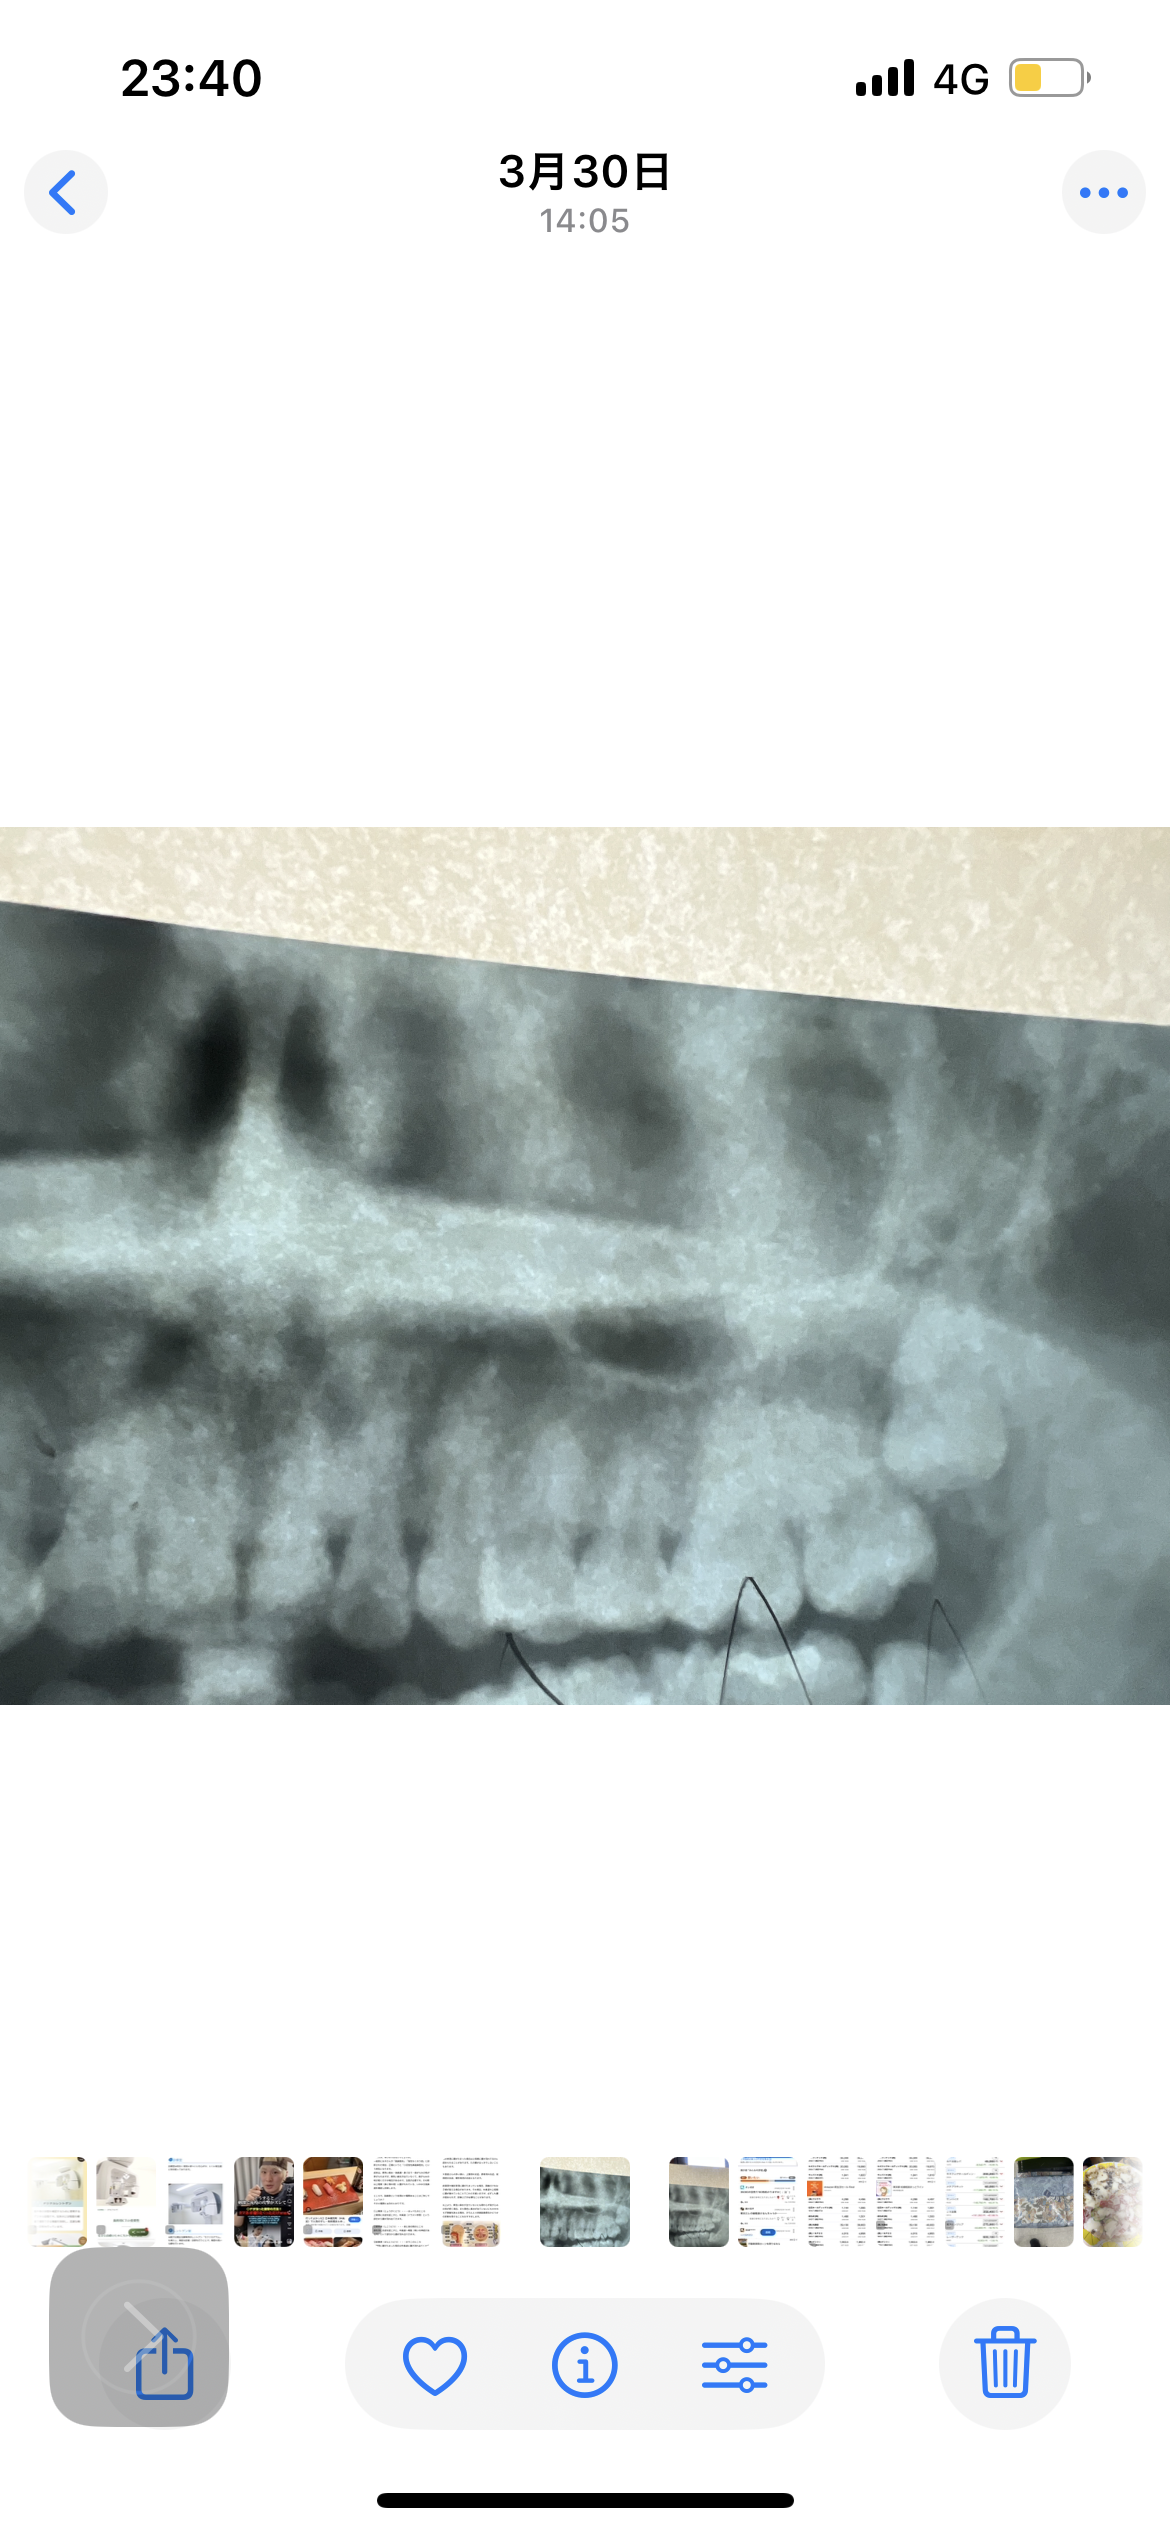

後鼻漏や鼻づまりがあります。歯性上顎洞炎の可能性はありますか?